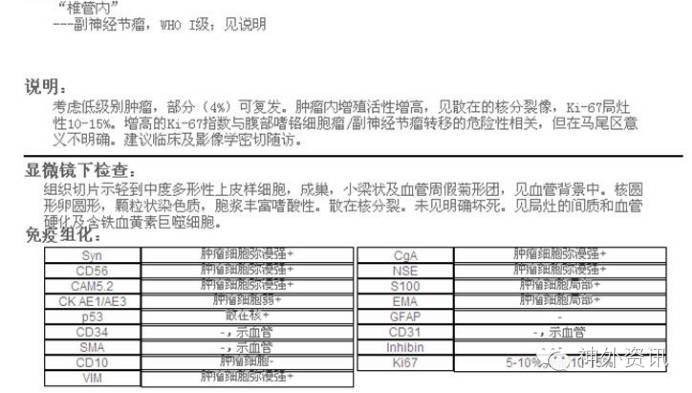

由于该患者临床体征及检查结果未发现转移性肿瘤相关证据,病理诊断有待进一步明确,逐请美国UCLA进行神经病理联合会诊。UCLA结果报告为椎管内副神经节瘤,WHOⅠ级,免疫组化及相关结果见图5。

图5. 美国UCLA病理会诊结果,考虑副神经节瘤。